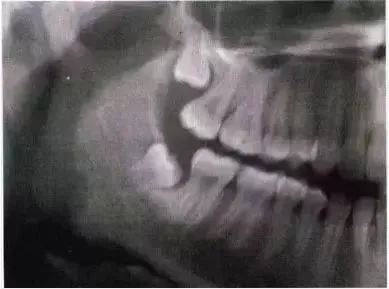

远中倾斜第三磨牙

手术的难易程度主要取决于骨的因素。手术的难度随埋伏深度的增加而增加。第Ⅰ、Ⅱ及第Ⅲ类阻生牙与第二磨牙和下颌升支之间的距离相对应。

全颌曲面断层×线片。切割牙冠时应经过阻生牙远中面的牙颈部的釉牙骨质交界处。